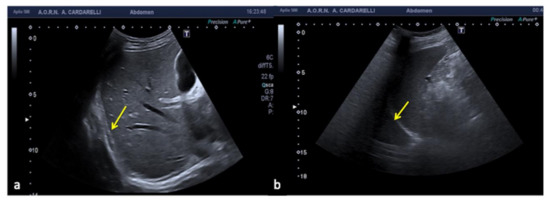

Figure 25. Rouleaux formation over the venous valves (a, arrows). After distal compression, the blood was squeezed and the rouleaux was finally cleared (b,c).